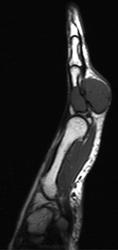

Периостальная хондрома (син.: юкстакортикальная хондрома, паростальная хондрома редкая доброкачественная опухоль, состоящая из зрелой хрящевой ткани и расположенная над надкостницей. Обычно она разрушает наружную часть коркового слоя, но не прорастает в костно-мозговой канал. Мужчины болеют в два раза чаще женщин. Типичная локализация - проксимальный конец плечевой и бедренной кости дистальный конец бедренной кости, а также фаланги. В редких случаях одновременно поражается несколько костей. Периостальная хондрома обнаруживается большей частью в метафизарной части, лишь у 30 % больных поражаются диафизы. Опухоль достигает в среднем 2-3 см в диаметре. Она окружена зоной остеосклероза и сопровождается периостальным остеогенезом, так что на границе опухоли с костью образуется грушевидное углубление с четкими контурами. Под микроскопом периостальная хондрома имеет тонкие контуры, она как бы погружена в корковый слой и покрыта надкостницей, как тонкой скорлупой. На разрезе ее ткань синюшно-серая или белая, хрящевые элементы обладают дольчатым строением. Участки обызвествления имеют вид желтовато-белых вкраплений. Эта опухоль состоит из гиалинового хряща, дольки которого разделены фиброзными прослойками или костными балками, местами обызвествленными. Кое-где отмечается проникновение опухолевых клеток в костномозговой канал, на большем же протяжении внутренний контур образован компактной костью.